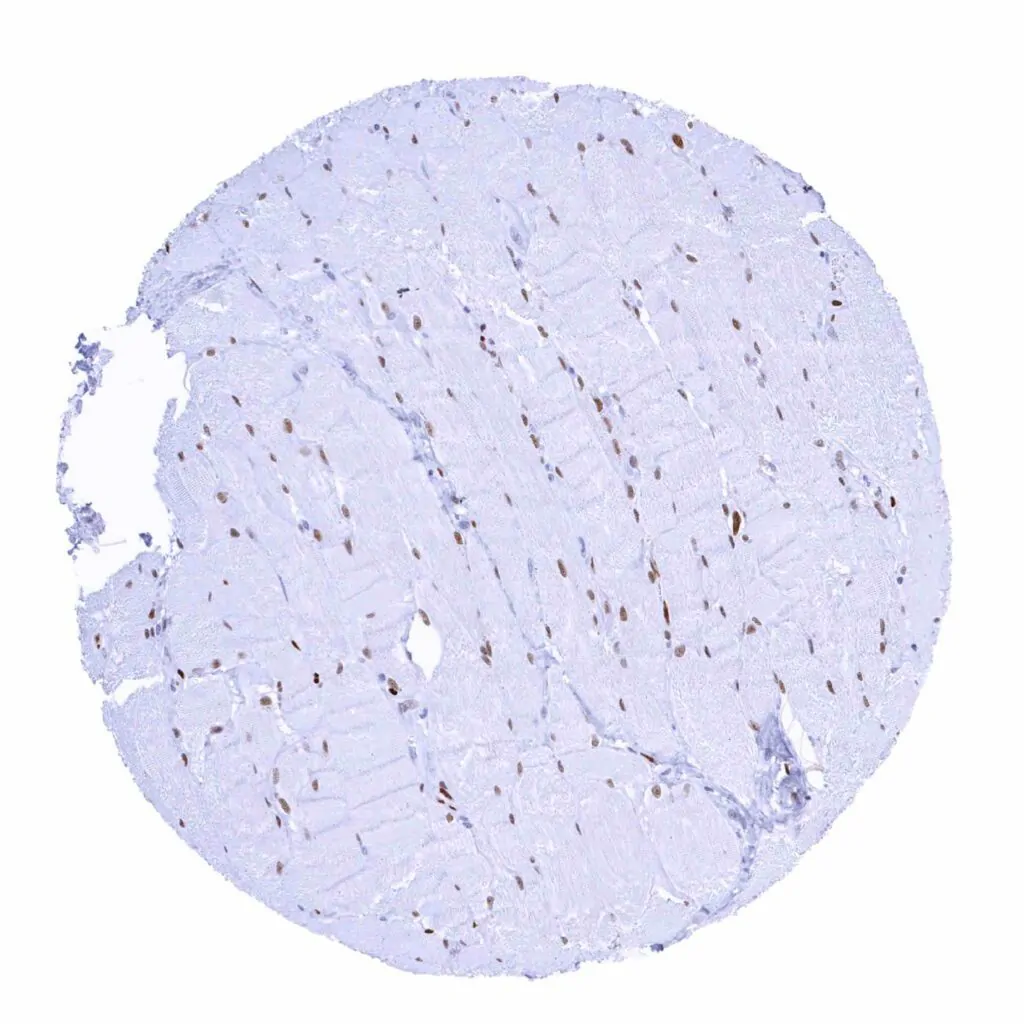

Skeletal muscle – Significant MCM2 staining in a large fraction of skeletal muscle cells